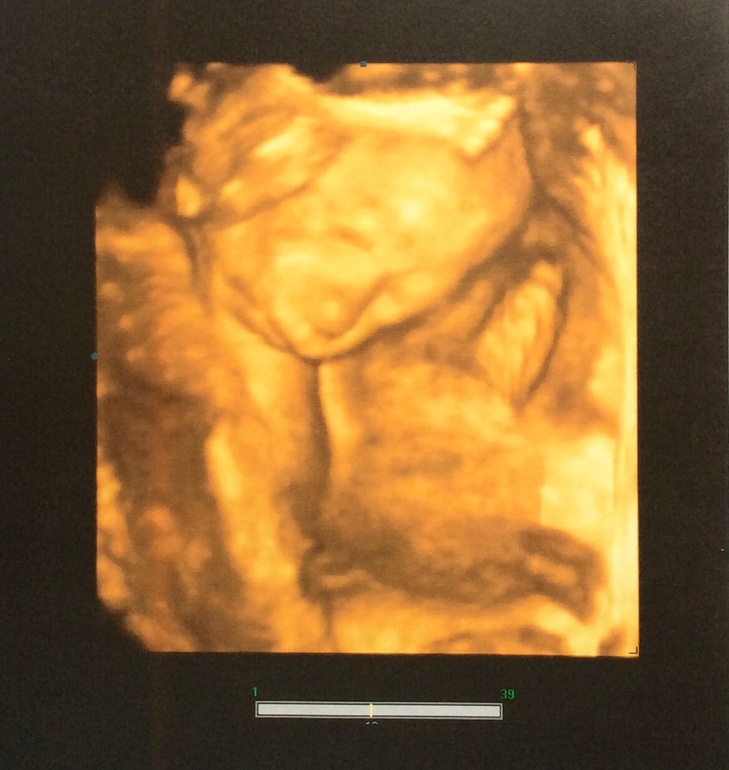

Ну а дальше, можно сказать, первые фото нашей принцессы:

Малышка очень похожа на своего папу! Я когда увидела на мониторе, просто обалдела, как будто детскую фотку мужа показали) лежит головкой вниз, также как и Тёма в позе "боксера" (ручки сжаты в кулачки у лица, в течение узи иногда закидывала их за голову). Удачное я выбрала время для узи, малышка и не спала крепко и не особо бодрствовала, а как сказала врач, отдыхала и дремала. Обвития нет, количество вод нормальное, степень зрелости плаценты соответствует сроку, ЧСС 153 уд/мин, вес уже 598 гр, длина 29 см (на 20 гр и на 1 см уже больше Тёмы). Это меня немного испугало, т.к. Тёма родился крупный 4140 гр и 57 см. Но пока рано делать выводы, посмотрим еще по последнему узи. Зато головка меньше, чем у Тёмы)) Все остальные показатели в норме и соответствуют сроку.